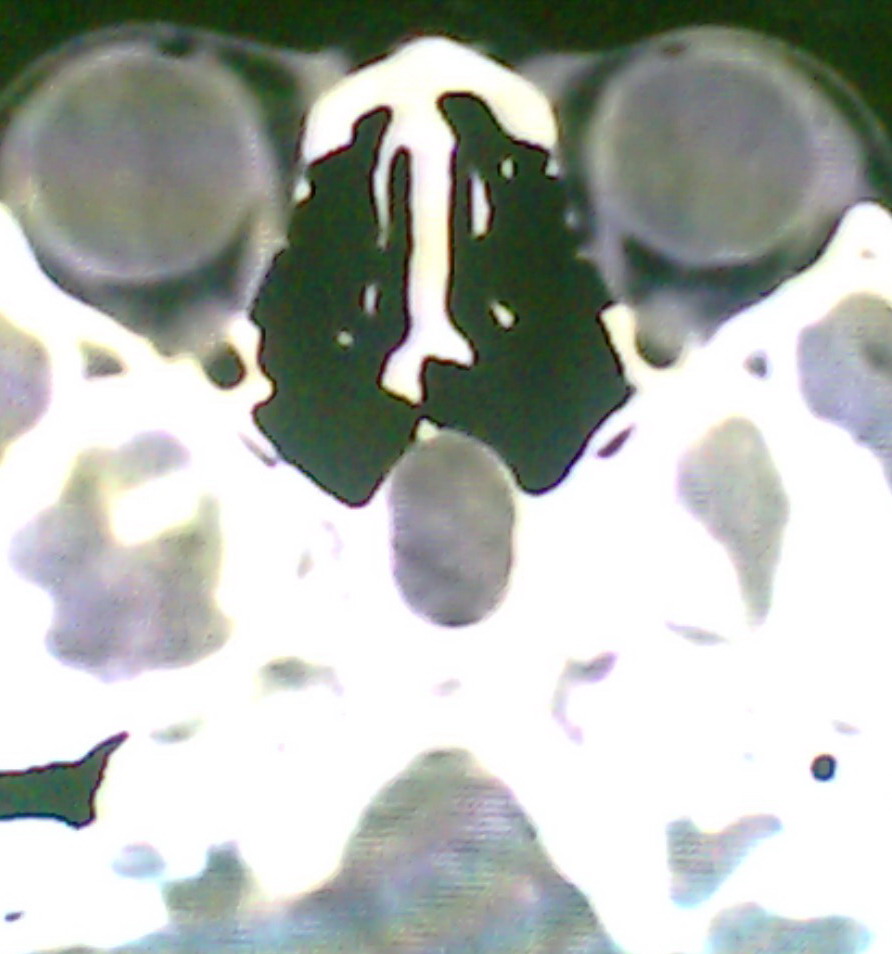

女、18岁,身高1.5左右,鼻塞、流涕数月,两侧瞳孔明显增大,曾与几年前去北京看眼,未发现病变。

考虑起源与蝶窦的粘液囊肿。

考虑脑膜脑脊液鼻内膨出

考虑起源于蝶窦的粘液囊肿突入鼻咽部。

\"几年前去北京看眼\"不知这句话有何玄机,支持考虑脑膜脑脊液鼻内膨出,膨出口在蝶鞍处

建议冠状面扫描,支持:脑膜鼻内膨出; 蝶窦粘液囊肿突入鼻腔可能性小。

在上级医院冠状位ct扫描后,诊断为:脑膜膨出,已住院准备手术。等待术后结果。